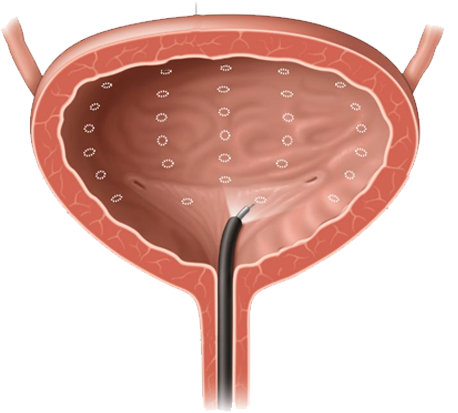

Tengo como compromiso mejorar la salud de nuestra comunidad y promover la prevención de patologías que afectan al aparato urinario, glándulas suprarrenales y retroperitoneo de ambos sexos, y el aparato reproductor masculino.

“La detección oportuna

de cáncer de prostata

salvó mi vida”

- Raúl Gómez Soriano

“Gracias a la prevención, el doctor pudo identificar una infección en etapa temprana”

- Lourdes Campos Uribe